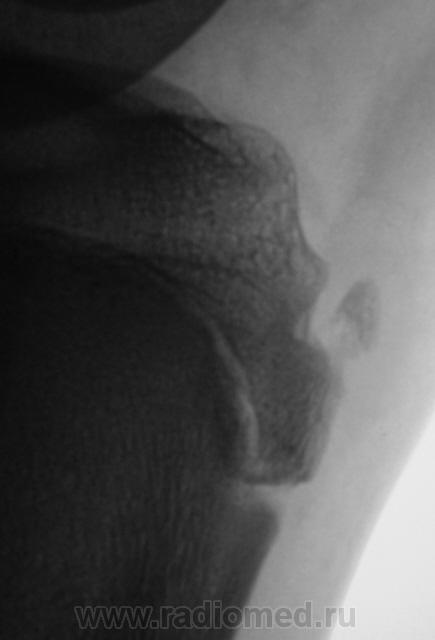

Пациент направлен на рентгенографию коленного сустава с диагнозом - Болезнь Осгут - Шлаттера.

фрагментация бугристости Б\Б кости

Болезнь Осгут - Шлаттера, как-то не вдохновляет. Более склонен к консоидирующемуся отрывному перелому бугристости б/берцовой кости.

Более склонен к варианту окостенения, хотя травматический генез, как и асептический некроз (абсолютно согласен с Максималистом - при наличии клиники и анамнеза) с повестки дня окончательно, до выяснения оных, не снимаются.

Уважаемые коллеги! На мой взгляд, выявленное на рентгенограмме, образование костной плотности, с четкими, ровными контурами, однородное по своей структуре отношения с бугристости большеберцовой кости не имеет. Хотелось бы знать возраст пациента, его анамнез (спорт, травмы области коленного сустава). Больше похоже на обызвествления собственной связки надколенника. Дополнил бы УЗИ коленного сустава.

16 лет "учтенному лицу", ранее жалоб не было, рядом "мама", которой доктора посоветовали..., вот и вся история...